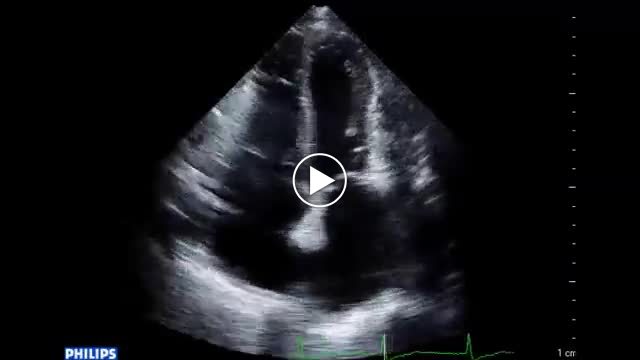

• 図5 心エコー、手術所見 a